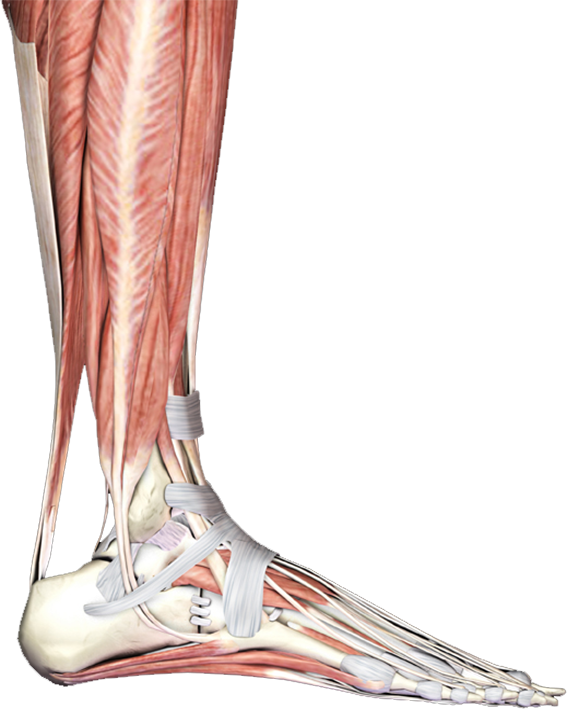

跟腱

足底筋膜炎